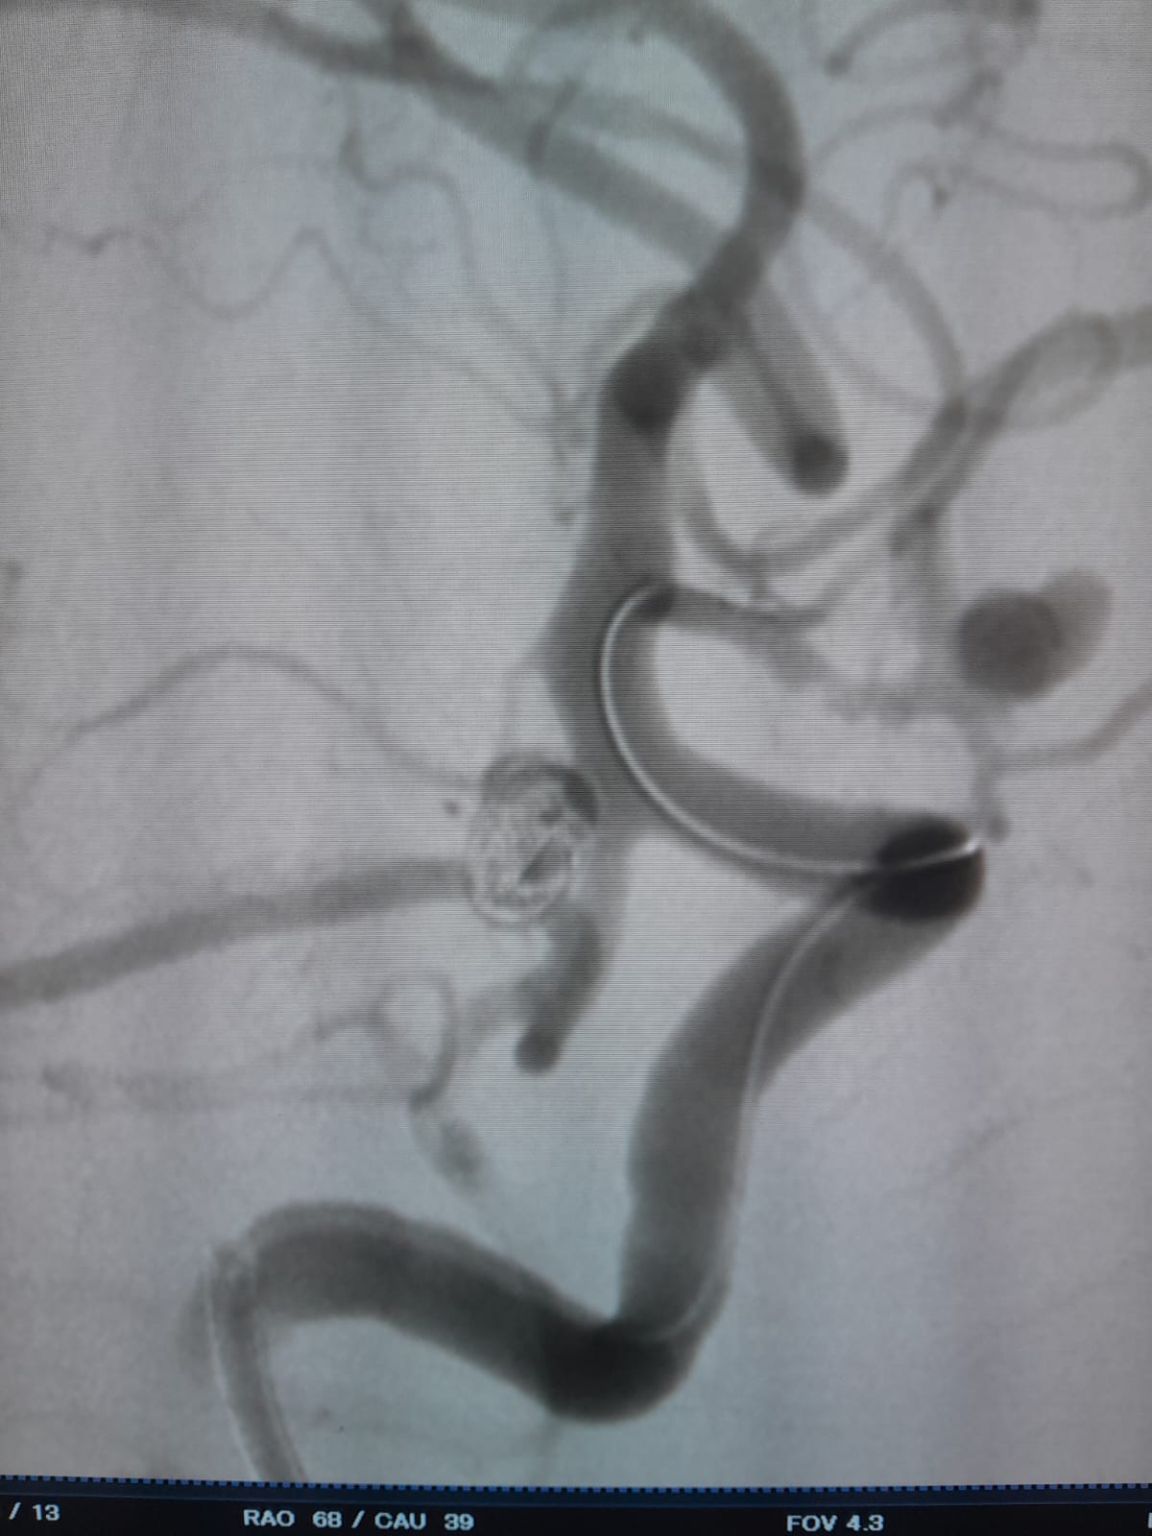

The vascular access was established and the team then successfully navigated the Frepass® Disposable Microcatheter (TJMC14) to the target site. Embolization was performed using three Perdenser® Embolic Coil System (TJCST4.508-3D, TJCST0306-3D, TJCST0206-3D) deployed with the Deromper® Coil Detachment Controller (TJCDC).

Posterior Communicating Artery Aneurysm (Re-treatment)

During follow-up, residual filling was noted in the previously treated posterior communicating artery aneurysm. The team re-accessed the site using Frepass® Disposable Microcatheter (TJMC18 Plus) and successfully deployed a Nuva® Flow Diverter (TJED-D-4.5-16), which demonstrated ideal wall apposition and excellent flow diversion, leading to highly satisfactory treatment outcomes.